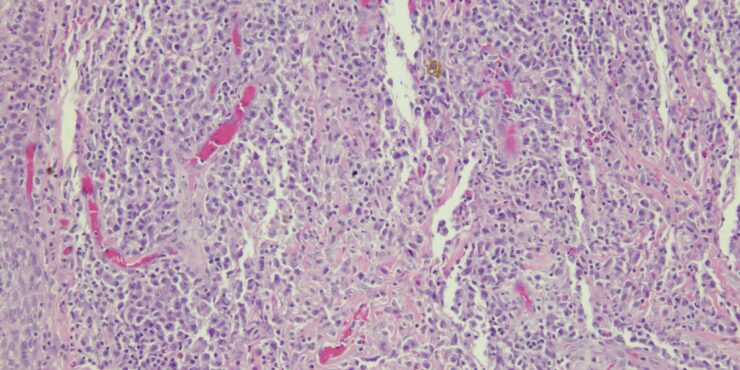

Lupus vulgaris = ุงูุฐุฃุจ ุงูุดุงุฆุน Lupus Vulgaris LV is an extremely chronic, progressive form of cutaneous tuberculosis occurring in individuals with moderate immunity and a high degree of tuberculin sensitivity. Differential Diagnosis of Tuberculosis Verrucosa Cutis ยท Warts or keratoses ยท Hyperkeratotic lupus vulgaris ยท Blastomycosis ยท Chromomycosis ยท Bromoderma ยท Lesions due to […]